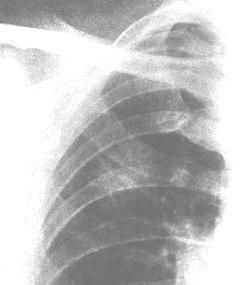

诊断资料的主要来源是病史和胸部X线.病史中如有早期局部症状,会引起对肿瘤的怀疑;胸部X线检查可明确病变部位,并可显示其对周围组织结构的影响,但多个肿瘤中心的大规模研究并未证实胸部X线和痰标本检查有助于筛查肺癌。尽管上述方法偶可早期发现肺癌,但早期发现对病人生存率并无影响。

当疑有肺癌时,在胸部摄片后即要获取组织以从组织学上确诊。体温常无特异性,偶可发现转移性病变的体征(肿大的淋巴结或肝脏肿大)。其他肺外体检表现已在前文讨论过.X线表现取决于受累的部位。

在无症状的病人,胸部X线常可见一个外周性小结节性肿块.如肿块直径<5~6mm,则难以发现.以往的X线检查结果对了解新生物颇有价值。对较小的孤立结节,穿透性强的X线和体层摄片可显示钙化,钙化的数量必须超过一个斑点,才能诊断为良性肿瘤或慢性肉芽肿性病变并排除肺癌。CT可显示其他技术看不到的病变,并可根据有无淋巴结扩散的迹象有助于肿瘤的分期。偶尔需要胸部磁共振成像(MRI)检查,对显示肺尖Pancoast瘤有无胸壁及椎体侵犯最有帮助。

有症状的病人,胸部X线可显示支气管狭窄和不规则肺实质浸润,或肺不张。在阻塞区或在周围型肿瘤内部可能看到空洞形成。阻塞性肺气肿不常见。偶尔,X线可显示在不相邻的肺叶内有浸润或阻塞区,此种现象不能用单个肿瘤灶解释而是支气管树弥漫性粘膜下淋巴渗透的结果.胸膜渗液往往与浸润性或外周部肿瘤有关,胸液的细胞学检查或胸膜活检可提供诊断。极少数情况下,在尚未发现肺内病灶时,痰中即可找到肿瘤细胞。